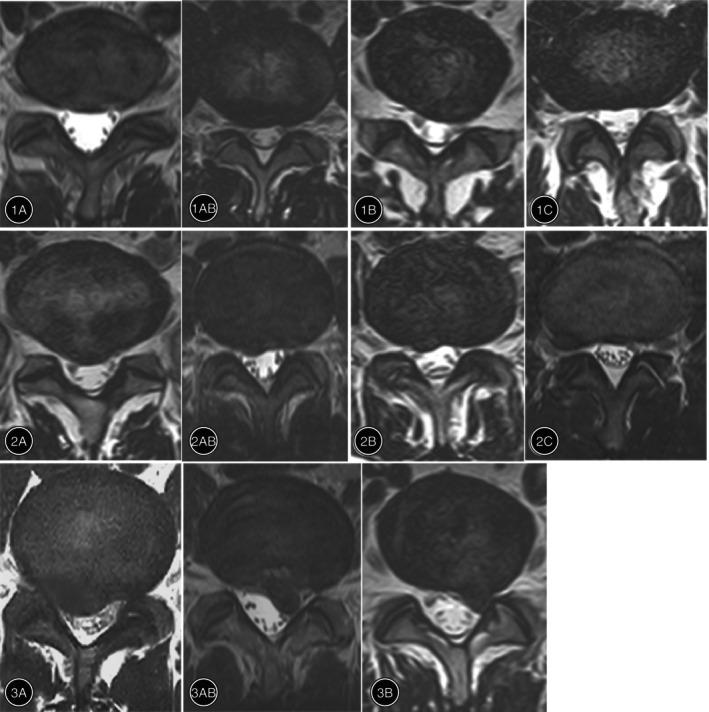

Classified into seven groups according to the MSU classification, it was found that there was an improvement in the VAS and ODI scores at four postoperative follow-ups (p < 0.001). PELD showed better results than TLIF in reducing pain and improving the ODI scores in the classifications of 3B, 2B, and 2C (p < 0.05). TLIF demonstrated consistent superiority over PELD in 2A, 2AB, 3A, and 3AB classifications (p < 0.05). The total recurrence rate in the PELD group (11.05%) within 5 years after surgery was higher (p < 0.05) than that in the TLIF group (3.96%). These were mainly concentrated in the 2A, 2AB, 3A, and 3AB types. Moreover, the rate of excellent and good outcomes in the PELD was higher than in the TLIF but no significant difference (χ = 1.0568, p = 0.5895).

根据MSU分类分为七组,发现在四个术后随访时间点VAS和ODI评分均有改善(p < 0.001)。在3B、2B和2C分类中,PELD在减轻疼痛和改善ODI评分方面比TLIF效果更好(p < 0.05)。在2A、2AB、3A和3AB分类中,TLIF显示出比PELD持续的优势(p < 0.05)。PELD组术后5年内的总复发率(11.05%)高于TLIF组(3.96%)(p < 0.05)。这些主要集中在2A、2AB、3A和3AB类型。此外,PELD的优良率高于TLIF,但差异无统计学意义(χ = 1.0568,p = 0.5895)。